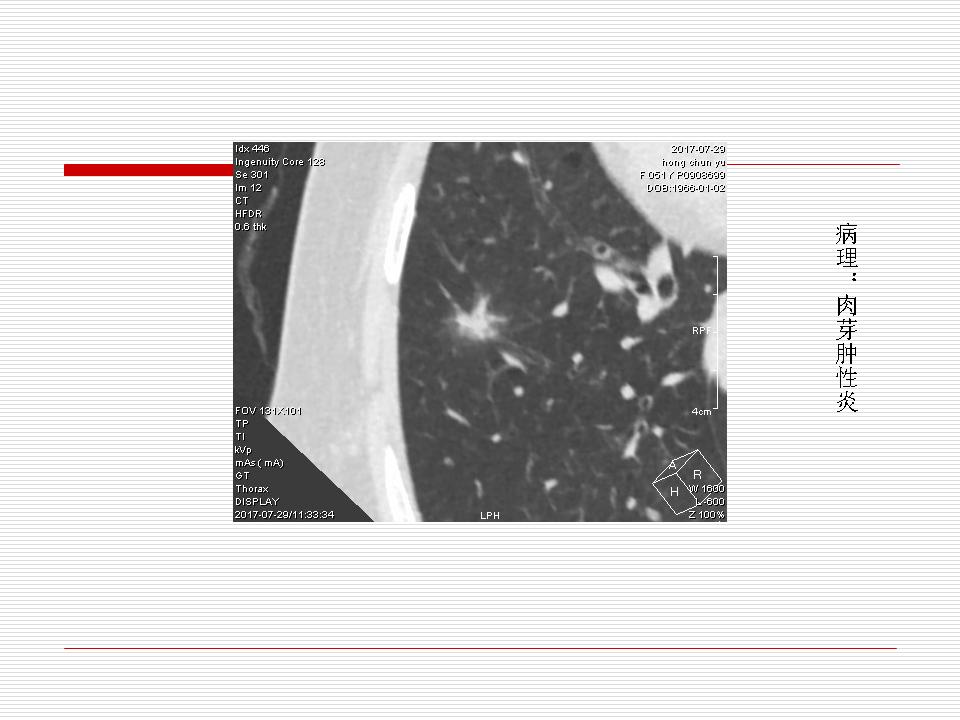

肺部阴影永恒且最重需要鉴别的是:到底是炎症还是肿瘤?但临床的病例中的影像表现难以界定或有些肿瘤特征,同时又有些炎症特点是非常常见的情况。作为临床医生我们怎么去总结分析,并找到之所以是炎症或之所以是肿瘤的细微差别或特点非常重要,也非常有用。2019.12.7浙江省2019年胸心外科学学术年会在宁波召开时,我的临床病例分析与经验总结<那些像肺癌的炎症与像炎症的肺癌>获得在大会交流的机会,以下为该PPT的内容,与你分享,希望对同道有益,有借鉴与启迪。若有探讨与进一不完善的建议,欢迎文末留言讨论: